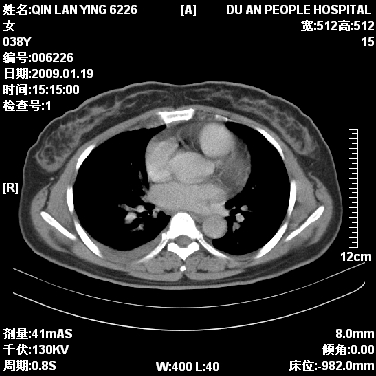

女,38岁,胸疼1个月。wbc:1万4

1)右肺中央型肺癌并右肺上叶阻塞性肺炎、节段性肺不张,纵隔淋巴结转移、右侧胸膜转移、肝脏转移。2)右侧胸腔少量积液。

1、右侧中央型肺癌并阻塞性肺不张,纵隔内、主动脉弓旁、右肺门淋巴结及肝脏转移可能性大,建议纤支镜进一步检查。

2、右侧胸腔积液。

本病例有几个容易诊断的地方:1、右肺上叶前段支气管闭塞,肺不张。2、淋巴结明显肿大。3、肝脏多个类圆形低密度影呈“牛眼征”改变,高度提示转移。